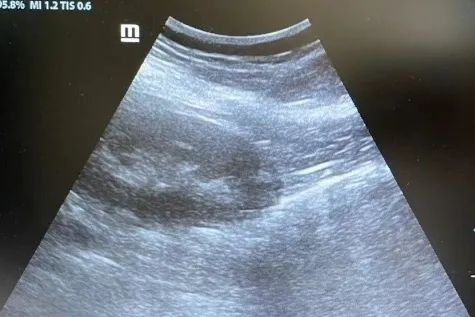

超声引导下肾穿刺后肾周血肿

腹腔镜下肾穿刺后肾周无明显血肿